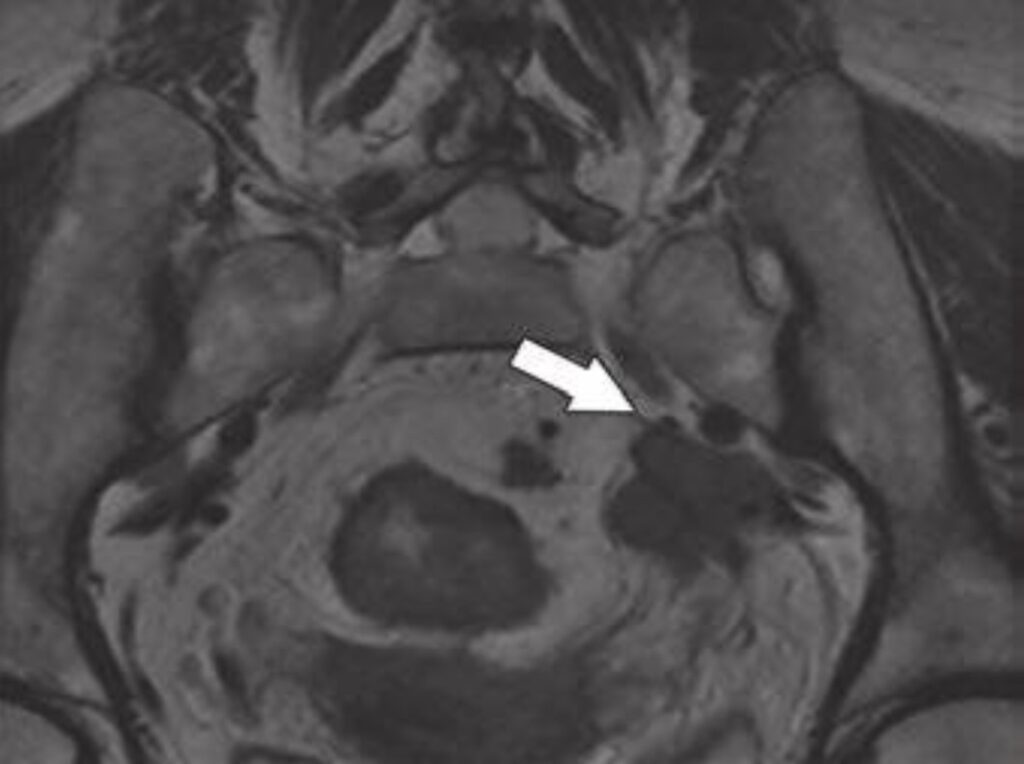

Fig. 2—Morphologic features of metastatic mesorectal nodes on MRI

and potential pitfalls in assessment. 58-year-old woman with rectal

adenocarcinoma. Oblique axial T2-weighted MRI (left) shows apparently

spiculated node (arrow). Graininess of image is related to poor signal-tonoise

ratio (SNR). Coronal T2-weighted MRI (right) shows that same node is

homogeneously T2 hyperintense with dark capsule (arrow), which is typical

of reactive mesorectal node. This image has superior SNR. Suboptimal images

can lead to erroneous assessment of nodal morphologic features. This

patient proceeded directly to surgery. Total of 38 lymph nodes (0.3–1.3 cm)

were harvested. Eleven of larger lymph nodes were serially sectioned before

submission for histologic processing. Final pathology revealed T3N0 disease.